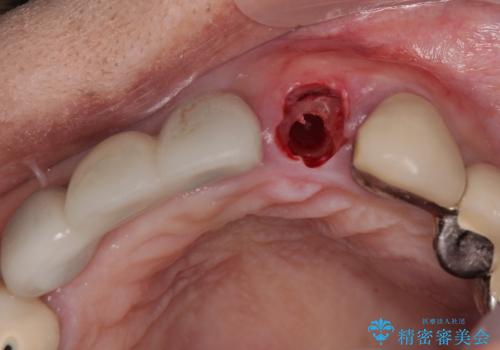

- 以前から頻繁に前歯が土台から外れてしまうことがあり、インプラントによる治療を希望して来院された患者様です。

歯根が割れていることはありませんでしたが、残っている歯質が全て歯肉よりも深い位置にあるため、土台としての機能は不足している状態でした。

歯根周辺の骨や歯肉の状態は良く、抜歯して速やかにインプラントを埋入し、即日で仮歯を装着するプランにて治療を行うこととしました。

初回カウンセリング時にはセラミッククラウンが装着されていましたが、インプラント治療でのご来院時には前歯は外れて紛失をしてしまったとのことでした。